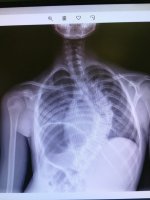

Pierwszą w Polsce operację bez usztywniania kręgosłupa u dziecka ze skoliozą przeprowadzono w Uniwersyteckim Dziecięcym Szpitalu Klinicznym w Białymstoku. Po zabiegu pacjent może wrócić do pełnej aktywności fizycznej.

W końcu marca w Białymstoku wykonano operację korekcji skoliozy idiopatycznej techniką bez usztywniania kręgosłupa, tzw. VBT (ang. Vertebral Body Tethering). To autorskie opracowanie światowej sławy chirurgów kręgosłupa z USA dr Darryl Antonacci i prof. Randal Betz z Institute for Spine and Scoliosis. Metoda ta polega na wszczepieniu w kręgosłup ruchomych prętów elastycznych (wymiennie używa się też określenia śruby elastyczne i taśmy elastyczne), bez usztywniania kręgosłupa. - Pręty umożliwiają dziecku powrót do normalnej aktywności w ciągu sześciu tygodni, nawet z gimnastyką artystyczną i tańcem włącznie - opisywała zabieg prof. Anna Wasilewska, dyrektor szpitala dziecięcego.

Operacji poddano 11-letnią dziewczynkę z Białegostoku. Wykonali ją dr Darryl Antonacci w asyście ortopedów z Kliniki Ortopedii i Traumatologii Dziecięcej UMB dra Pawła Grabali i szefa kliniki dra Tomasza Guszczyna. Tego typu zabiegi, prócz USA, wykonują ledwie cztery ośrodki w Europie, zaś dr Grabala jest jednym z kilku osób na świecie, która odbyła staż u prof. Antonacci’ego.